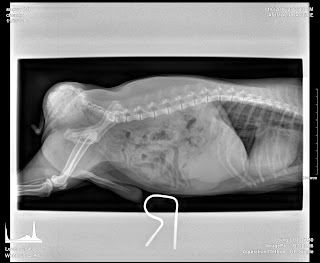

Air contrast bladder X-rays show no stones and no inflamed bladder wall.

Dog likely to have urinary tract infection.

Miniature Schnauzers are very prone to urinary stones, but in this case, there was none.

The owner had been feeding Royal Canin Urinary S/O, hence preventing struvite stone formation.

Follow up 7 days later, on the diagnosis of cystitis.

The dog lis back to normal now.